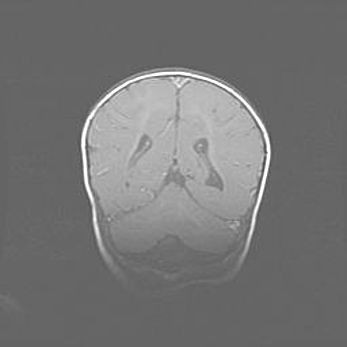

Сообщающаяся гидроцефалия. Кистозная энцефаломаляция головного мозга.

Возраст: 3 месяца 4 дня

Вес: 3100 г

Пол: женский

Окружность головы: 34 см

Срок гестации: 31 неделя

Кистозная энцефаломаляция головного мозга - одна из форм поражения головного мозга в детском возрасте. Характеризуется возникновением множественных и распространённых кист в коре, белом веществе и подкорковых образованиях головного мозга у плодов, новорождённых и детей раннего возраста. Развитие кистозной энцефаломаляции связано с внутриутробной асфиксией и гипотонией, родовой травмой, тромбозом синусов, пороками развития сосудов, инфекциями, сепсисом и другими причинами. Наиболее значимые инфекционные агенты: вирусы простого герпеса, цитомегалии, краснухи, токсоплазмы, энтеробактерии, золотистый стафилококк и другие.